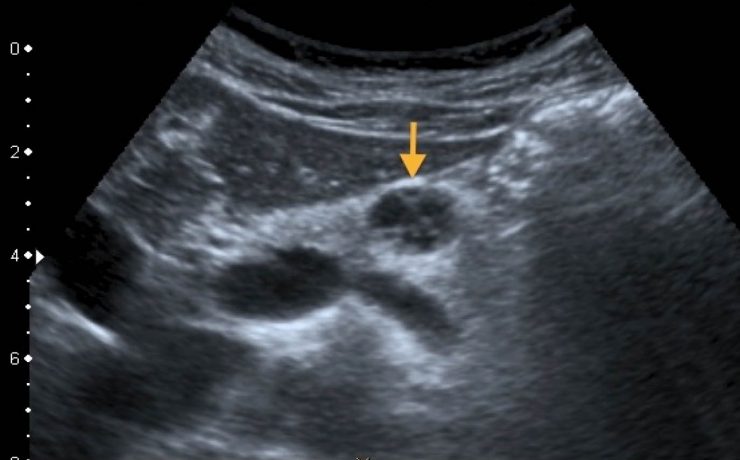

Las vías biliares intrahepática transcurren adyacentes a las raíces de la vena porta y las ramas de la arteria hepática. Los conductos hepáticos derecho e izquierdo se unen para formar el conducto hepático común a nivel del hilio hepático, el cual mide aproximadamente 30mm de longitud y se une al